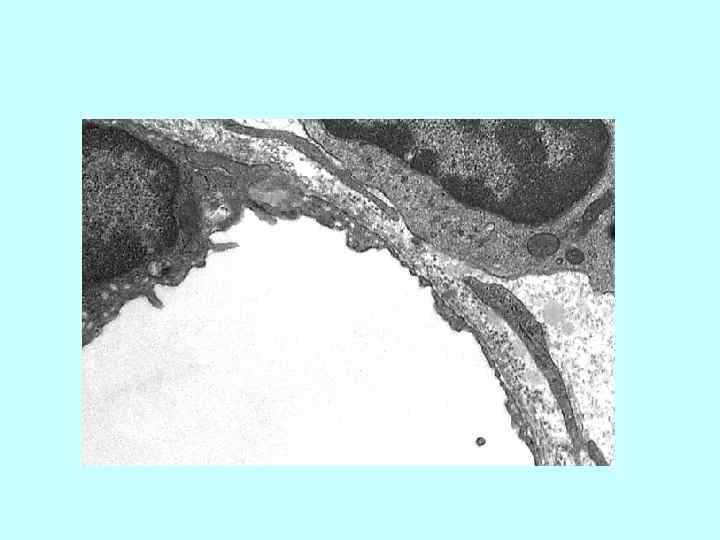

ВЕНА МЫШЕЧНОГО ТИПА. Поперечный срез бедренной вены кошки. Окр. Г. -Э. • Просвет вены ВЕНА МЫШЕЧНОГО ТИПА. Поперечный срез бедренной вены кошки. Окр. Г. -Э. • Просвет вены обычно спавшийся из-за более слабого развития средней оболочки. Внутренняя оболочка состоит из уплощенного эндотелия и очень тонкого субэндотелиального слоя. Средняя оболочка относительно тонкая и образована 3 -4 слоями гладких миоцитов. Наружная оболочка с сосудами сосудов наиболее развита. ЗАРИСОВАТЬ и ОБОЗНАЧИТЬ: 1. внутренняя оболочка эндотелий; субэндотелиальный слой; 2. средняя оболочка 3. наружная оболочка • сосуды сосудов